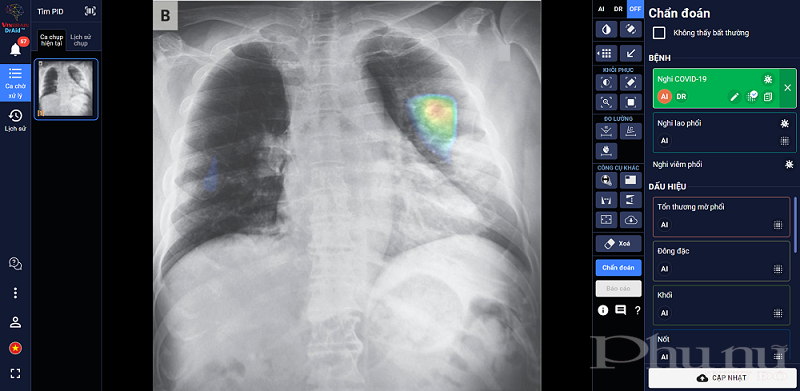

DrAid™ – phần mềm AI trợ lý bác sĩ đầu tiên tại Việt Nam - docác chuyên gia, nhà khoa học của VinBrain (công ty công nghệ thuộc Tập đoàn Vingroup) nghiên cứu phát triển thành công. DrAid hiện có khả năng hỗ trợ chẩn đoán 20 dấu hiệu bất thường và bệnh lý về tim - phổi - xương với độ chính xác trên 88% trong vòng 5 giây, đồng thời tự động đưa ra báo cáo y tế theo chuẩn quốc tế JCI có khoanh vùng và đo kích thước chính xác tại khu vực bất thường. Ngoài ra, tính năng “Hỏi ý kiến Bác sĩ thứ 2 (từ xa)” của DrAid™ hỗ trợ các bác sĩ gửi ảnh chụp trực tiếp từ máy chụp cho một bác sĩ khác để tham khảo ý kiến đối với những ca bệnh khó. Việc này giúp giữ nguyên chất lượng hình ảnh, đồng thời đơn giản hóa quy trình hội chẩn, giúp cho việc hội chẩn giữa hai bác sĩ diễn ra nhanh gọn, xóa bỏ các rào cản về địa lý và thời gian, đồng thời nâng cao chất lượng hội chẩn với gợi ý về chẩn đoán của AI.

Đặc biệt, DrAid™ mang lại 4 giá trị ưu việt trong phát hiện và điều trị COVID-19 dựa trên ảnh X- quang ngực thẳng gồm: Phát hiện nhanh góp phần sàng lọc mầm bệnh trong cộng đồng, song song cùng phương pháp xét nghiệm PCR. Kết hợp cùng xét nghiệm PCR từ đó nâng cao độ chính xác, giảm thiểu tình trạng âm tính giả tránh bỏ sót; Hỗ trợ đánh giá tiên lượng tình trạng bệnh nhân thông qua lịch sử hình ảnh chụp X-quang, để từ đó có hướng điều trị phù hợp; Hỗ trợ tăng tính nhất quán và chuyển giao kiến thức của bác sĩ từ tuyến Trung ương tới cơ sở.

DrAid™ chẩn đoán và tiên lượng điều trị bệnh nhân COVID-19 dựa trên hình ảnh X-quang ngực thẳng.